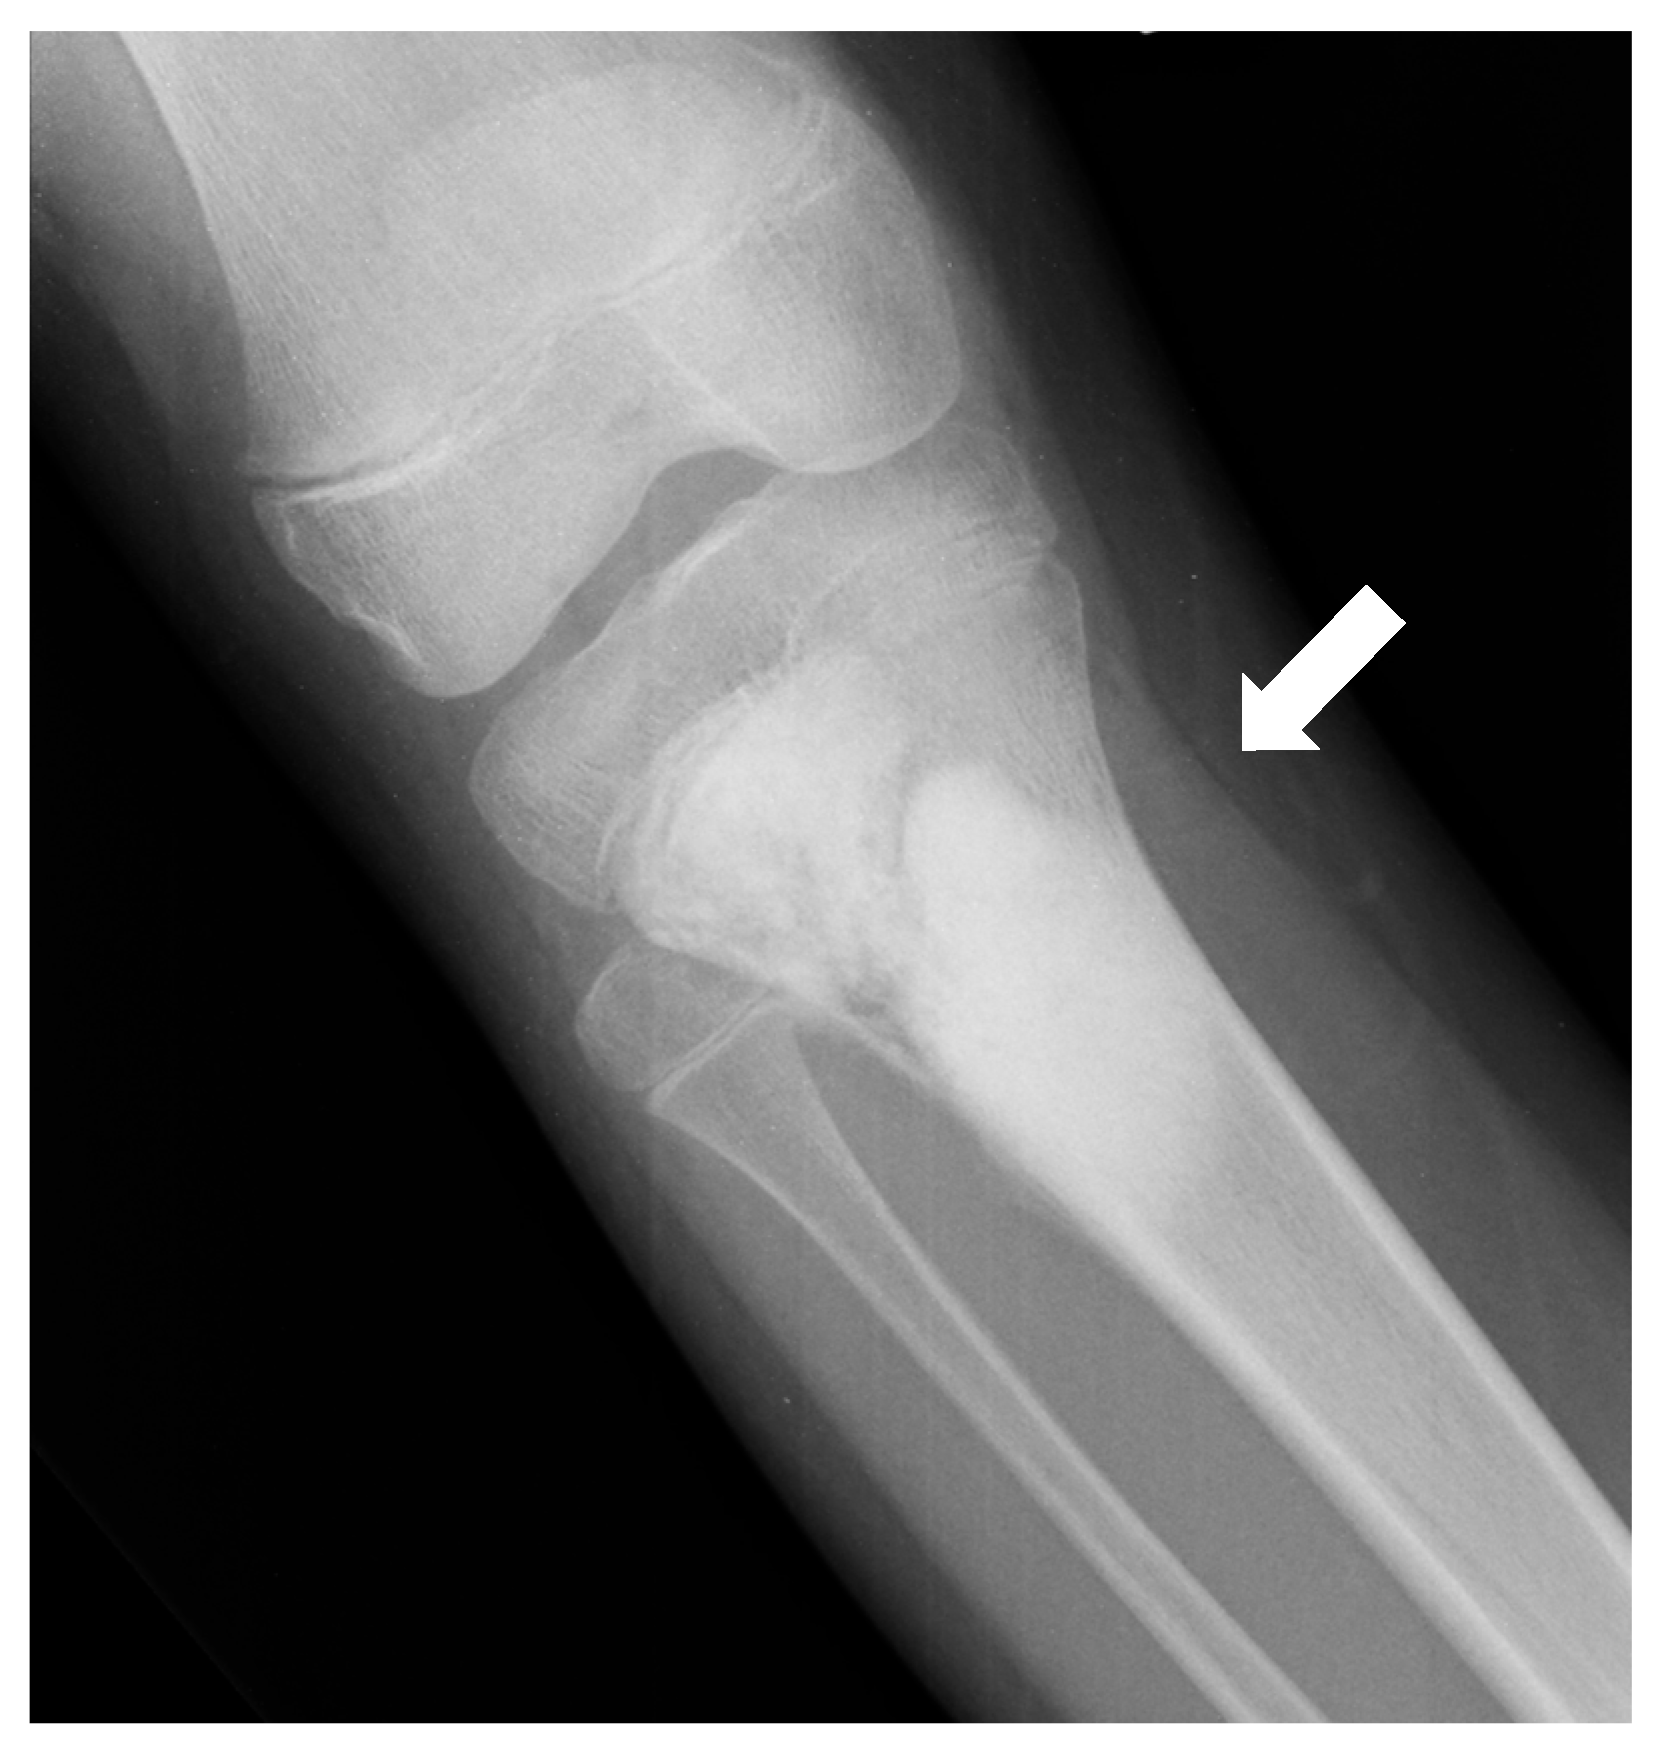

| Conventional osteosarcoma | Mixed (lytic and sclerotic) or completely eburneous | Sunburst, Codman triangle, other irregular/aggressive types | Soft-tissue components frequently displayed |

| Parosteal | Lobulated osseous mass fused with cortical bone, usually with large dimensions, broad implant base | None, non-aggressive ones, or only cortical thickening | Cauliflower-like mass, thin linear cleavage between portions of tumor and cortical bone, frequent intramedullary involvement |